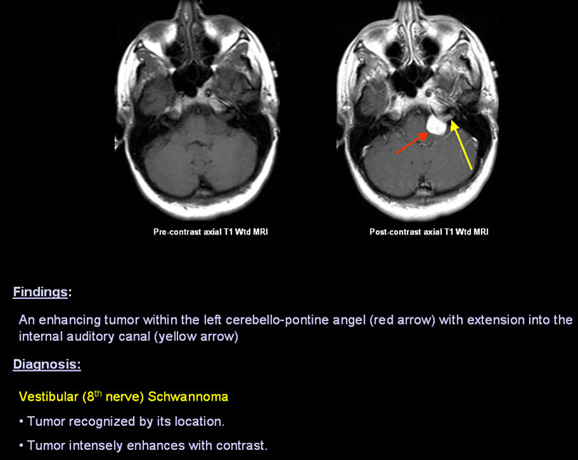

Benign Tumors